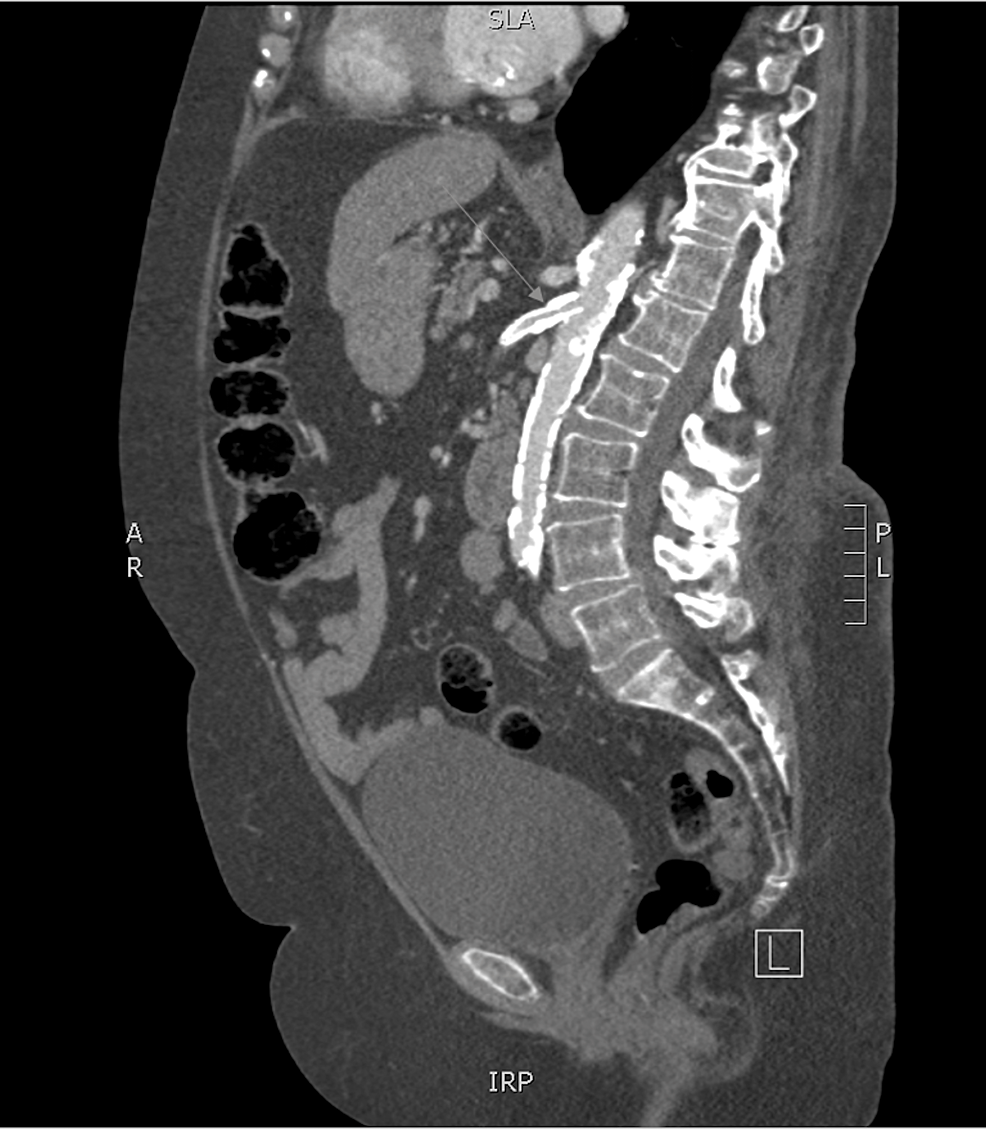

(PDF) Mesenteric ischemia an unusual presentation of fistula between Smoking Related Mesenteric Ischemia acute mesenteric ischemia is the sudden onset of small intestinal hypoperfusion. chronic mesenteric ischemia, also called intestinal angina, refers to episodic or continuous hypoperfusion of. more than 90% of cases of chronic mesenteric ischemia are related to progressive atherosclerotic disease that affects the origins of the. endovascular and hybrid methods are being increasingly used to treat. Smoking Related Mesenteric Ischemia.